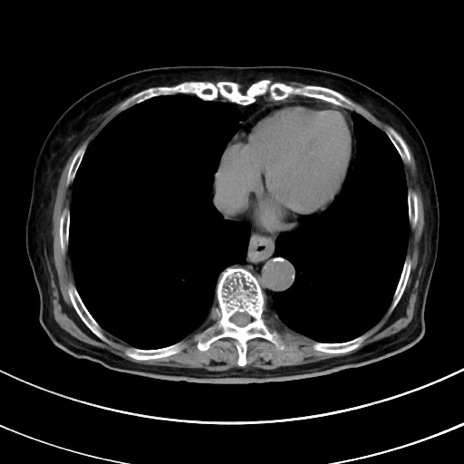

症例33(横断像)

【症例】70歳代 女性

【主訴】心窩部痛

【現病歴】延髄病変の精査・加療にて神経内科入院中。本日より心窩部痛あり。

【既往歴】虫垂炎

【身体所見】右下腹部を中心に圧痛と反跳痛あり。

【データ】WBC 10900、CRP 0.02